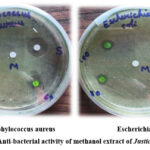

Inhibitory Effects of Palnt Extract Against Micro-Organisms

The quest for novel antibacterial agents has led researchers to explore the vast realm of plant secondary metabolites, renowned for their profound medicinal properties. This study aimed to evaluate the antibacterial efficacy of a methanol plant extract against two formidable pathogens, Escherichia coli (E. coli) and Staphylococcus aureus (S. aureus).

The antibacterial activity of the methanol plant extract was assessed using the disk diffusion method, with concentrations ranging from 60-100 µg/mL. The results revealed a concentration-dependent inhibitory effect, with the extract producing notable inhibition zones of 1-3 mm and 2-4 mm against E. coli and S. aureus, respectively.

In contrast, the standard antibiotic Amoxicillin exhibited a pronounced inhibition zone of 12 mm, serving as a benchmark for comparison. However, the plant extract demonstrated a dose-dependent response, where elevated concentrations yielded enhanced inhibition rates. This positive correlation underscores the extract’s potent antibacterial properties, warranting further exploration into its therapeutic potential.

Table 4: Inhibition rate of Methanol plant extract

Figure 12: Anti-bacterial activity of methanol extract of Justicia adhatoda.Click here to View Figure |

The methanol plant extract was found to possess a complex mixture of bioactive phytoconstituents, as revealed by preliminary phytochemical screening, predominantly alkaloids, flavonoids, tannins, saponins and terpenoids. UV-Visible spectroscopy identified absorption peaks at 273.7, 423.6 and 665.7 nm, indicating diverse chromophore structures. The FT-IR spectrum exhibited a characteristic absorption band corresponding to the hydroxyl (O-H) functional group, confirming its presence. GC-MS analysis elucidated phytochemical constituents, retention times, molecular formulas and weights. Notably, 1,2-Dimethoxy-4- Benzene exhibited potent binding affinity (-5.6 kcal/mol) with Mitogen-Activated Protein Kinase (MAPK), forming two hydrogen bonds with LYS 54 (A) at 2.49Å and 2.52Å, indicating potential drug-like properties. A significant antibacterial effect was observed with the methanol extract, particularly in inhibiting the growth of Staphylococcus aureus surpassing E. coli inhibition rates, underscoring its therapeutic potential as an efficient antimicrobial agent.